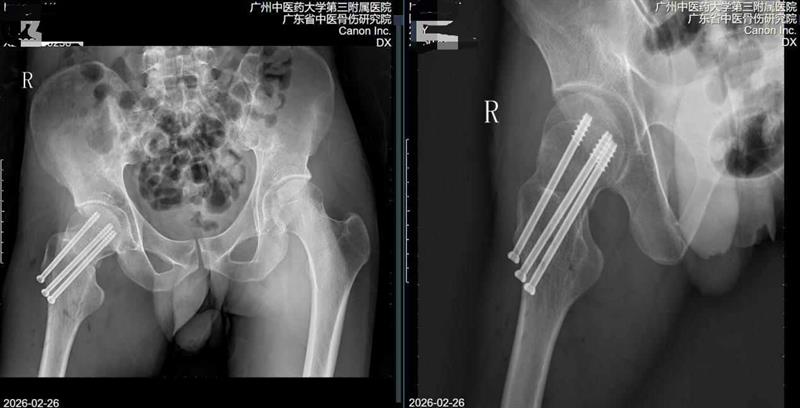

撞一下桌子就骨折? 年輕人喝酒導致骨質疏松?

阿豪與往常一樣和朋友約著喝酒慶祝新年,上頭后大家開始打鬧了起來,打鬧中不小心被推了一把,右髖撞上了桌角。“當時具體情況記不太清了,但是撞完以后我還能正常走路,就直接睡覺沒管了。”阿豪回憶道。然而,第二天,右髖部劇烈地疼痛襲來,他甚至無法站立,去當地醫院一拍片子診斷結果讓所有人倒吸一口涼氣:股骨頸骨折。

高齡髖部骨折患者術后即刻自主行走! 南方醫院創傷骨科髖關節MDT團隊探索快速康復新模式

近日,南方醫院創傷骨科髖關節外科胡稷杰主任醫師團隊與麻醉手術中心劉衛鋒副主任及護理團隊通力協作,成功為一名78歲股骨頸骨折高齡患者實施神經阻滯麻醉聯合鎮靜鎮痛技術DAA入路股骨頭置換術。手術全程僅用時30分鐘。術后患者意識清醒,在醫護人員指導與保護下自主行走離開手術室,患者及家屬對治療效果高度滿意。